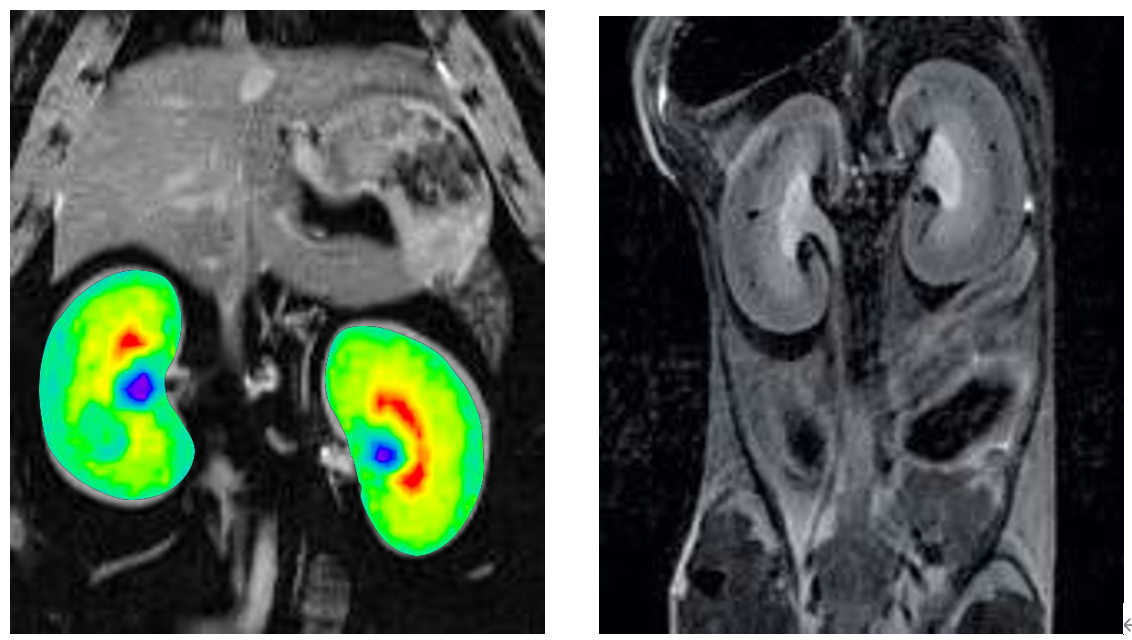

6、腹部成像

布鲁克同步触发采集技术可以消除腹部运动伪影,高场下T2对比度能更好显示腹部各个脏器。

大小鼠腹部成像: